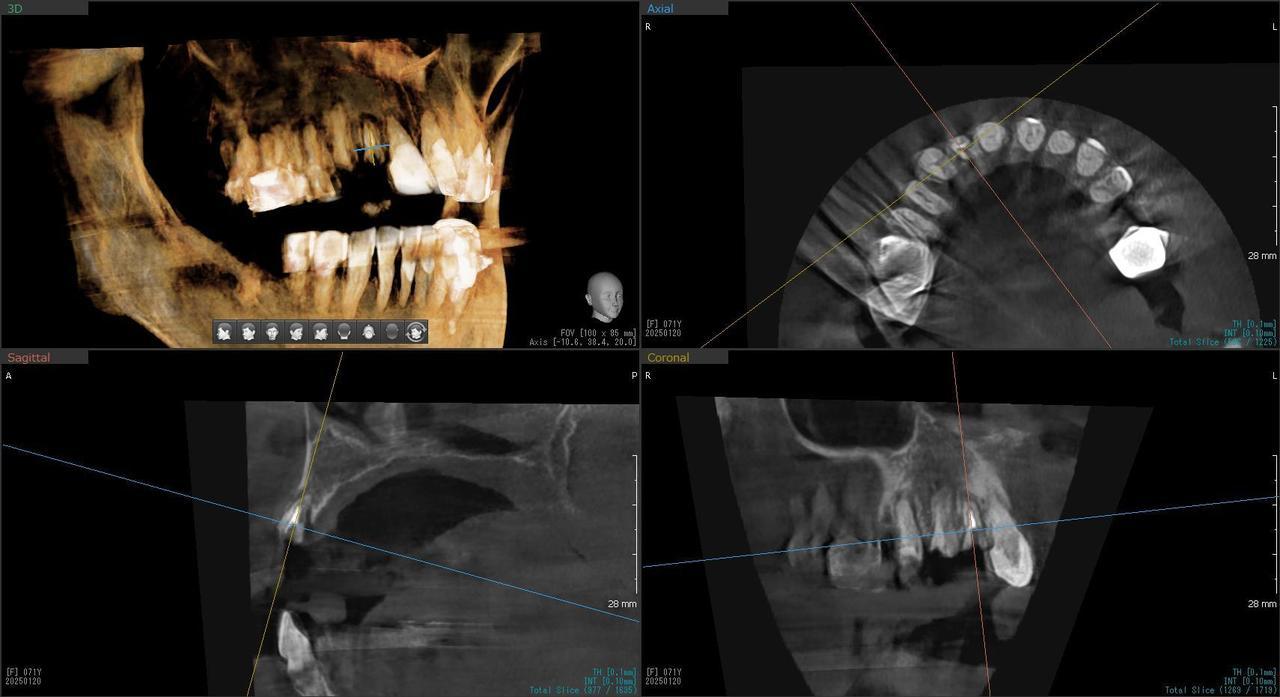

5.右上6番の歯根が破折したに大きな骨欠損を生じたケースに対して、通常なら、大幅な増骨手術(GBRとサイナスリフト)が必要で、最低1年は、かかるケースを、骨補填材なしで、インプラント埋入後、2.5か月で治療を終えたケース

After

枚方市のインプラントの症例

H・M様 女性 60代

症状としては、左上6番の歯根が歯根が破折したために、炎症が起き、上顎洞底までの及ぶ大きな骨欠損がおきていた、

治療法としては、動揺がひどくなってきて、炎症の症状もあったため、抜歯を希望。抜歯後にインプラント治療を希望したために、CTを撮影したところ、かなりの骨欠損が生じていた。インプラントは不可能か大幅な増骨手術が必要なるようなケースであったが、ご自分の骨が少し残っていた部分にエクストラワイドインプラントで固定をとることと、グラフトレスサイナスリフトを併用する計画を立て、インプラント埋入術を施行。2か月後、インプラントがデータ測定上安定したために、光学印象で印象を行い、2か月半後に上部としてジルコニアクラウンを装着して治療を終えています。

治療結果として、大幅な骨欠損があったが、2か月半という短時間で治療を終えることができた。通常のサイナスリフト等の大幅な増骨手術を行った場合、患者様に、肉体的、金銭的、時間的な負担をかけることになったが、グラフトレスサイナスリフトとエクストラワイドインプラントを使用することにより、そのことを避けることができた。

治療の期間・回数:治療回数インプラント埋入後6回

治療の価格:363000円(税込)

治療費の内訳:インプラント基本料(フィックスチャー(メガジェンインプラントANYONE) 及び手術費用、投薬費用、レントゲン費用、インプラント上部費用(アバットメントおよびジルコニアクラウンの費用用)330000円(税込み)左上6グラフトレスサイナスリフト費用 33000円(税込)